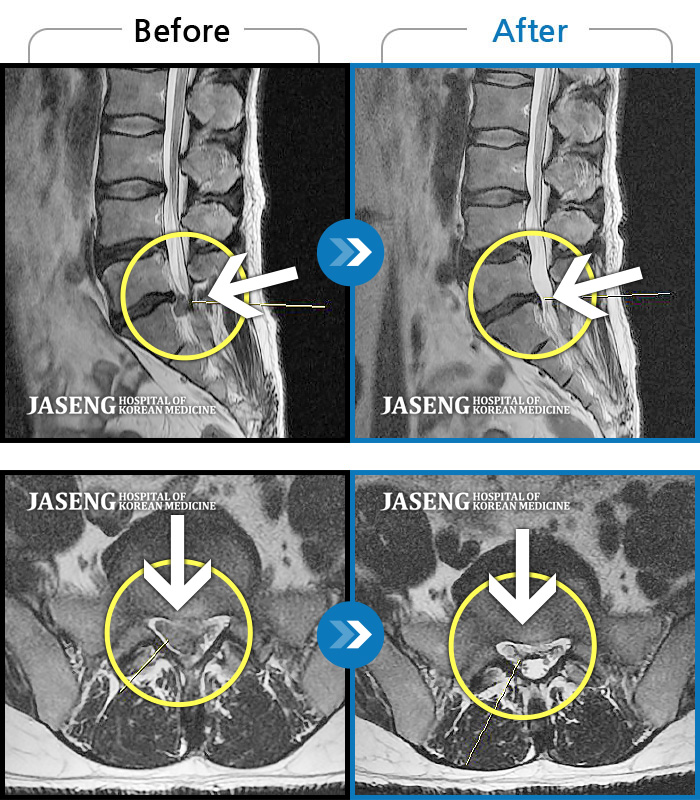

MRI 치료사례

우측 골반부터 다리 뒤쪽으로 발바닥까지 저림과 통증이 심해 걷기와 허리 굽히기가 어려운 상태